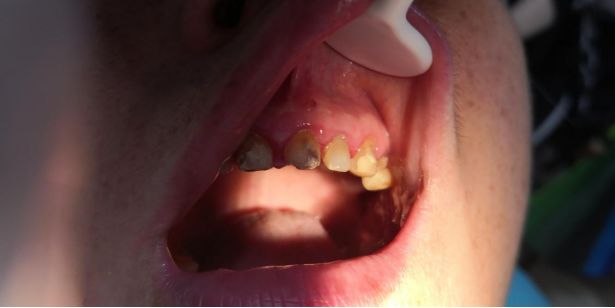

笔者最近接诊了一个患者,一位娭毑,上颌左右两边分别缺失了一颗磨牙,为了修复这两颗牙齿方便吃东西,她选择把剩余的健牙都磨小做成了基牙,形成了一座豪华版的“长江大桥”,但是这座大桥并不牢固,没过多久就脱落了,脱落之后来湖南航天医院就诊,要求重新粘结上这座“大桥”。

且不说这样的修复方法价格昂贵,这种修复方法对健牙的损伤也很大,为镶缺牙而先损大量好牙,实在可惜。万一后期某个牙齿出现问题,治疗起来还要先把整口义齿取下来,大大加重了治疗难度。而且患者牙龈边缘红肿,说明牙周状况和口腔卫生保持欠佳。